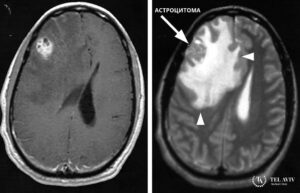

Заболевание, развивающееся в детском возрасте, относится к виду ювениальных, глиальных опухолей – астроцитом.

Это опухоль низкой степени злокачественности, которая может возникнуть в любом возрасте и локализуется преимущественно в отделах мозжечка, стволе головного мозга и в зрительном нерве. Новообразование имеет четкие границы, наличие кистозных узлов, характеризуется медленным ростом. Пилоцитарная астроцитома редко метастазирует в здоровые ткани, но способна достигать крупных размеров. Опухоль образуется из глиальных клеток – астроцитов, которые являются составной частью вещества, содержащегося во всех отделах головного мозга.